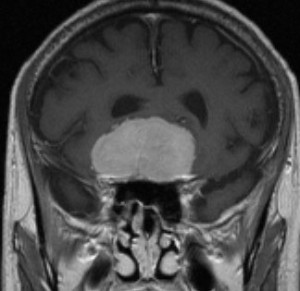

蝶形骨平面髄膜腫 planum sphenoidale meningioma

高度の両側の視力障害で発症しました。何の変哲も無い蝶形骨平面髄膜腫です。右下のCISS画像で視神経交叉が鞍背の後方まで変移しているのが解ります。また,蝶形骨平面はblisteringのため上方へ隆起しています。

この髄膜腫はしばしば,鞍結節部髄膜腫 tuberculum sellae meningioma あるいは嗅窩髄膜腫 olfactory gloove meningiomaと混同されます。鞍結節部髄膜腫との大きな違いは,feeding arteriesがposterior ethomoidal argerhyであり,蝶形骨平面からなので止血しやすいこと,視神経管の内部への腫瘍浸潤が生じないので,手術で視神経管を開放しなくてもよいことです。また,嗅窩髄膜腫との大きな違いは,両側前頭開頭で前頭葉を持ち上げるような手術を避けて,例えばこの例であれば,右前頭部から右前頭葉挙上のみで腫瘍摘出すれば片方の嗅索は温存できる可能性があることです(この例くらいまで大きくなると無理なことももちろんありますが)。